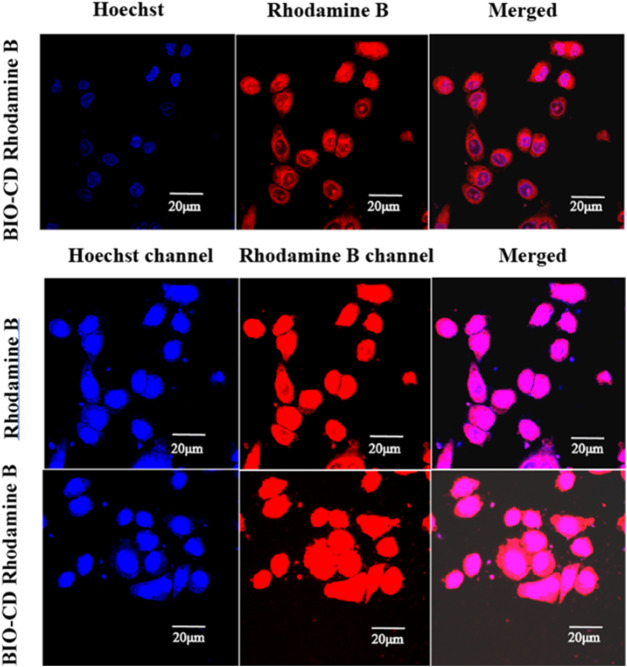

Cellular Uptake Assays

Rhodamine B (20 μg ml−1), Rhodamine B/BIO-CD inclusion complex (or Rhodamine B/β-CD inclusion complex) (20 equivalents) were co-cultured with LO2, HepG2 and Hela cells at 37°C for 2 h. Subsequently, cells washed three times with PBS, and cell uptake efficiency was observed with an inverted fluorescence microscope.

Two model drugs Rhodamine B and Hoechst dyes were used to explain the selective drug delivery efficacy of BIO-CD. The microscopic images showed that Hoechst crossed the cell membrane, indicating that Hoechst entered the cytoplasm. We observed that massive Rhodamine B accumulated in the cell surface when incubated with HeLa cells for 4 h in the delivery experiment of Rhodamine B. This result was significantly higher than Rhodamine B without using BIO-CD (Figure 13). Consequently, it proved that the BIO-CD could bind to biotin receptors selectively, mediated the absorption and accumulation of Rhodamine B in cells. Due to the enhanced cellular intake of the polymer-drug complex, the inclusion complex of AD-CBD/BIO-CD has much higher cytotoxicity than free AD-CBD.

Cellular Uptake Assays

We studied the capability of BIO-CD to promote the uptake of guest molecules in tumor cells. Rhodamine B was used as a model drug. Hela, HepG2, and LO2 cells were incubated with the inclusion complex of BIO-CD or ß-CD in media for 1 h. Meanwhile, we had observed a similar situation with ß-CD in normal cells LO2. As shown in Figure 14, after Rhodamine B entered the cavity of BIO-CD, it could enhance the efficiency of cell fluorescence imaging, while ß-CD was opposite. This might attribute to that BIO-CD specifically binded to the over-expressed biotin receptor on the surface of tumor cells, which resulted in the enhanced drug uptake. Because ß-CD did not have the targeting ability of biotin, and LO2 cell surface did not have the over-expressed biotin receptor, these possibly reduced the uptake capacity of cells. Data mentioned above confirmed BIO-CD successfully encapsulated guest drug and specifically bound to the biotin receptor to enhance the cellular uptake.